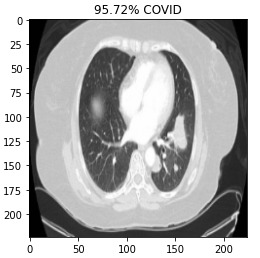

This is a Covid-19 virus detection application. Initially this application uses a machine learning model. The uses upload the Chest X-Ray or Brain scan Images to the user interface and the API take the input and proceed those input to ML model. The machine learning model process and analysis those inputs and generate output like a patient is a covid-19 +ve or covid-19 -ve. And finally the API take those inputs to the user interface. In this way this application basically works.